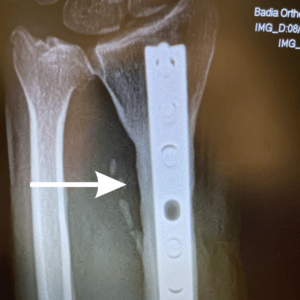

Follow up X-rays 27 years later

After X-Rays shows bone remodeling after 28 years. Graft was taken from iliac crest ( Pelvis).